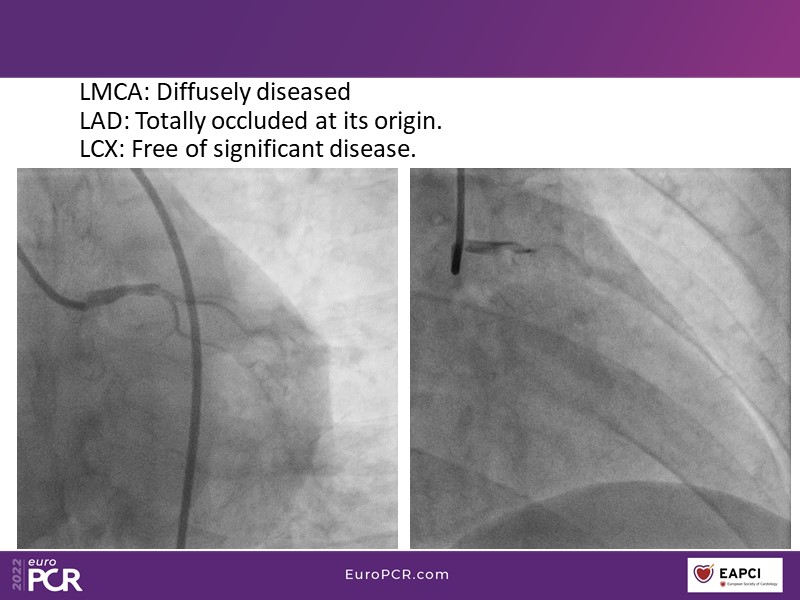

- To find out more about the application and mechanism of a sirolimus coated balloon for coronary artery disease treatment with case presentations in complex settings

- To understand how useful is a DES and DCB stent platform in complex coronary artery disease settings with case demonstrations and follow-up in diabetes mellitus